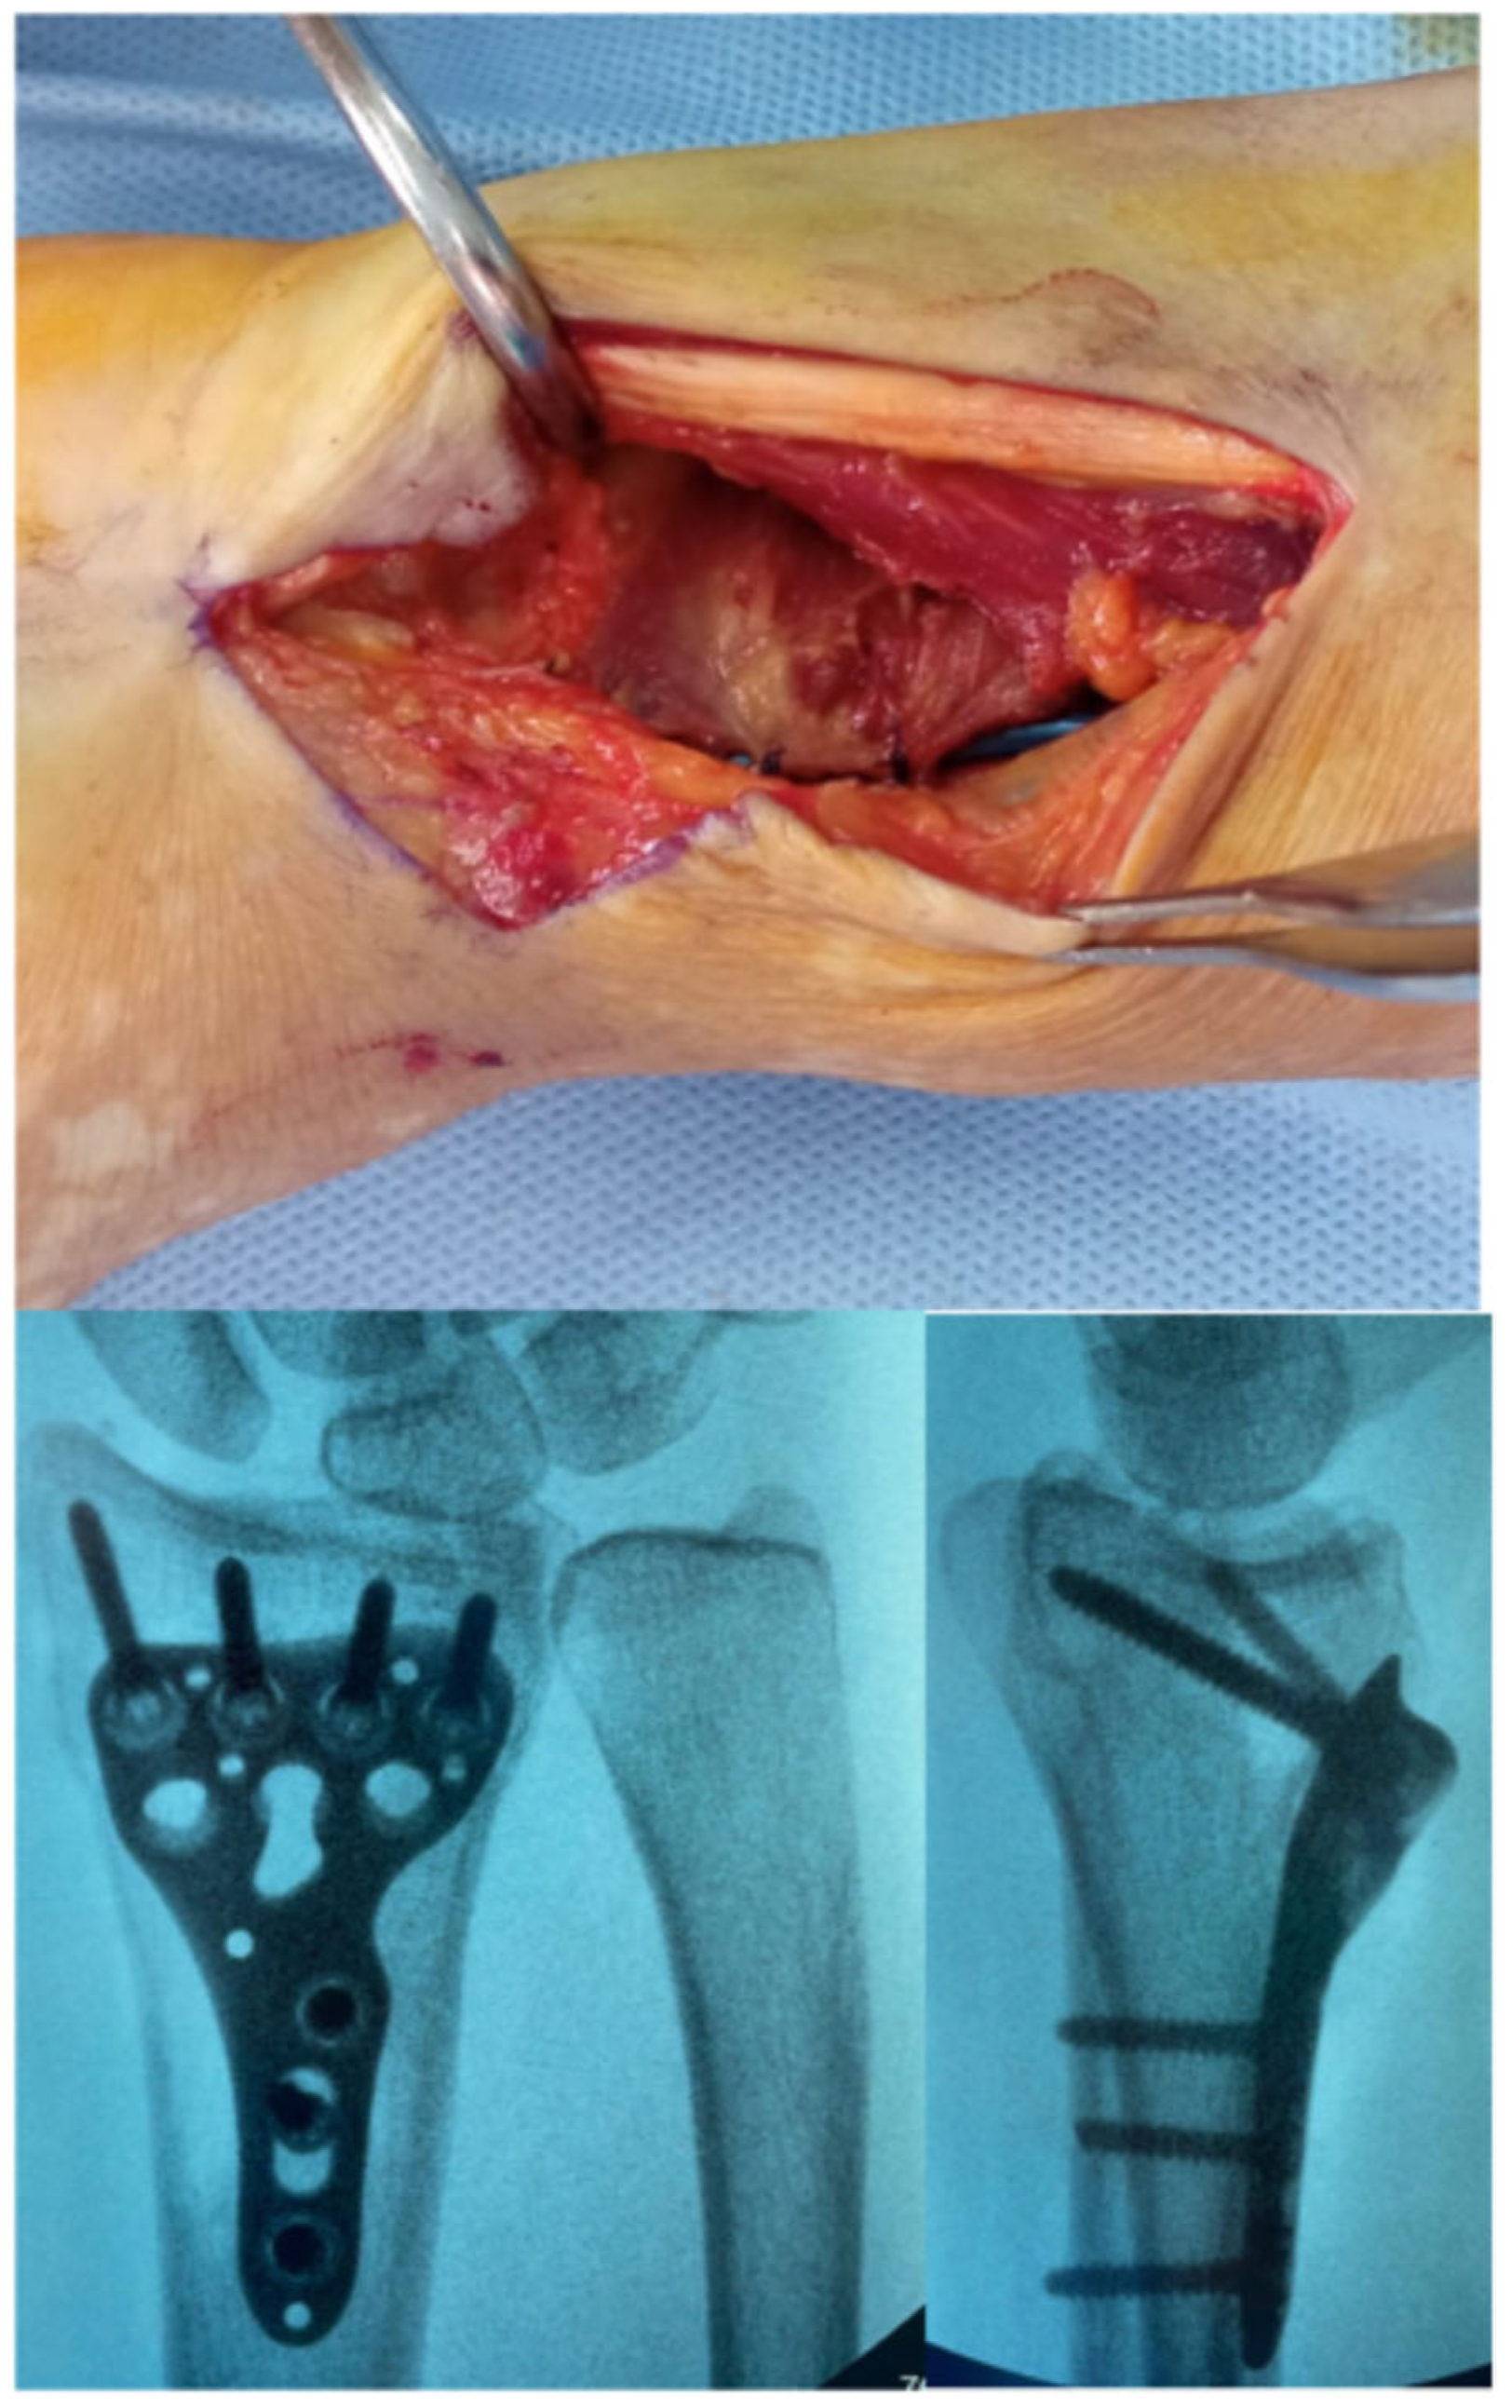

The superficial layer of the FCR sheath is longitudinally incised, and the FCR tendon is retracted ulnarly to protect the median nerve (Figure 2). The antebrachial fascia and the deep layer of the sheath are then exposed and opened (Figure 3). Adequate proximal exposure of the sheath is essential, and the distal floor should be opened carefully to avoid neurovascular injury.

The flexor pollicis longus (FPL) is gently retracted ulnarly using blunt dissection and a deep retractor, allowing exposure of the pronator quadratus muscle (Figure 4). Bipolar electrocautery is frequently required at this stage due to the increased number of perforating vessels encountered. The pronator quadratus is released along its distal and radial borders through an L-shaped incision, enabling full exposure of the distal radius and the watershed line.

Once the pronator quadratus is elevated, the anterior joint capsule becomes visible, and the brachioradialis (BR) release can be performed, providing direct visualization of the radial styloid (Figure 5). A retractor is positioned around the radial styloid to allow complete exposure of the volar aspect of the distal radius while simultaneously safeguarding the radial artery. At this stage, the first extensor compartment is also clearly identifiable.

The volar plate is then positioned according to standard variable-angle principles. Additional fixation of the radial styloid may be achieved using one or two 3.0 mm headless screws inserted percutaneously or, alternatively, with a dedicated radial styloid plate. The pronator quadratus is then re-approximated to cover the plate, minimizing the risk of flexor pollicis longus irritation. Final fluoroscopic images are obtained to confirm reduction and hardware placement (Figure 6).

Figure 3. Medial retraction of the FCR; exposure of the antebrachial fascia.

Surgeries 06 00104 g003

Figure 4. Pronator Quadratus exposure.

Surgeries 06 00104 g004

Figure 5. Pronator quadratus incision has been carried out, and the first compartment and BR can be visualized.

Surgeries 06 00104 g005

Figure 6. Final closure of the Pronator Quadratus and post operative X-ray control.

Surgeries 06 00104 g006